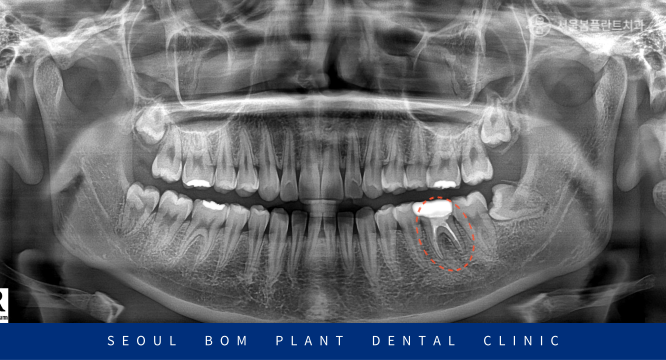

촬영 날짜 : 2022.11.30

정밀 검사를 위해

파노라마 사진과

작은 사진을 촬영하여

확인해 보았더니

아래턱 왼쪽 첫 번째 큰 어금니(#36)의

치근 분기부에서

까맣게 심한 골소실이 보였습니다.

예후가 좋지 않은 치아라

발치 가능성도 있었으나